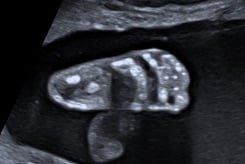

Herzschlag eines Feten im 3. Schwangerschaftsdrittel

High-End-Ultraschall

Ich arbeite mit einem „High-End-Ultraschallgerät“ der neuesten Generation, welches speziell für Pränataldiagnostik und Frauenheilkunde entwickelt wurde.